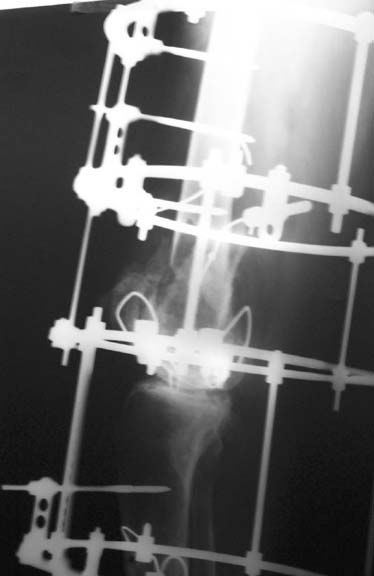

I have done closed reduction and Ilizarov ring fixator application in this case which I presented earlier. Patient is very comfortable. Skin has been opened only for K-wire / shanz screw introduction. Request your comments and opinions/criticisms.